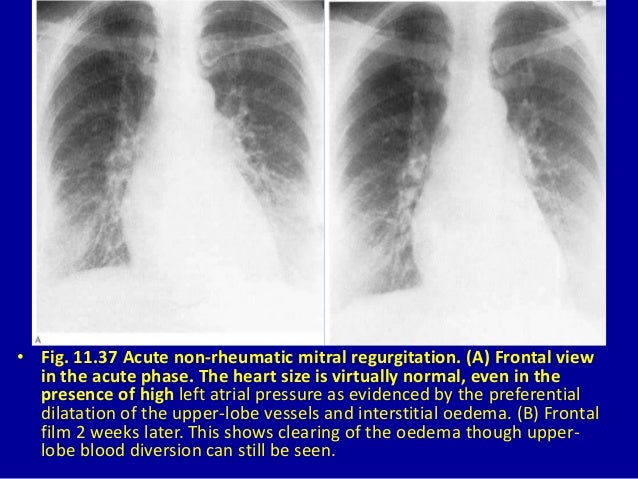

11 Acquired Heart Disease I

11 acquired heart disease i www.slideshare.net

Rheumatic Mitral Valve Disease | Radiology Key radiologykey.com

valve mitral rheumatic disease fig

Rheumatic Mitral Valve Disease | Thoracic Key

Rheumatic Mitral Valve Disease | Thoracic Key thoracickey.com

mitral valve rheumatic disease stenosis radiograph patient chest figure